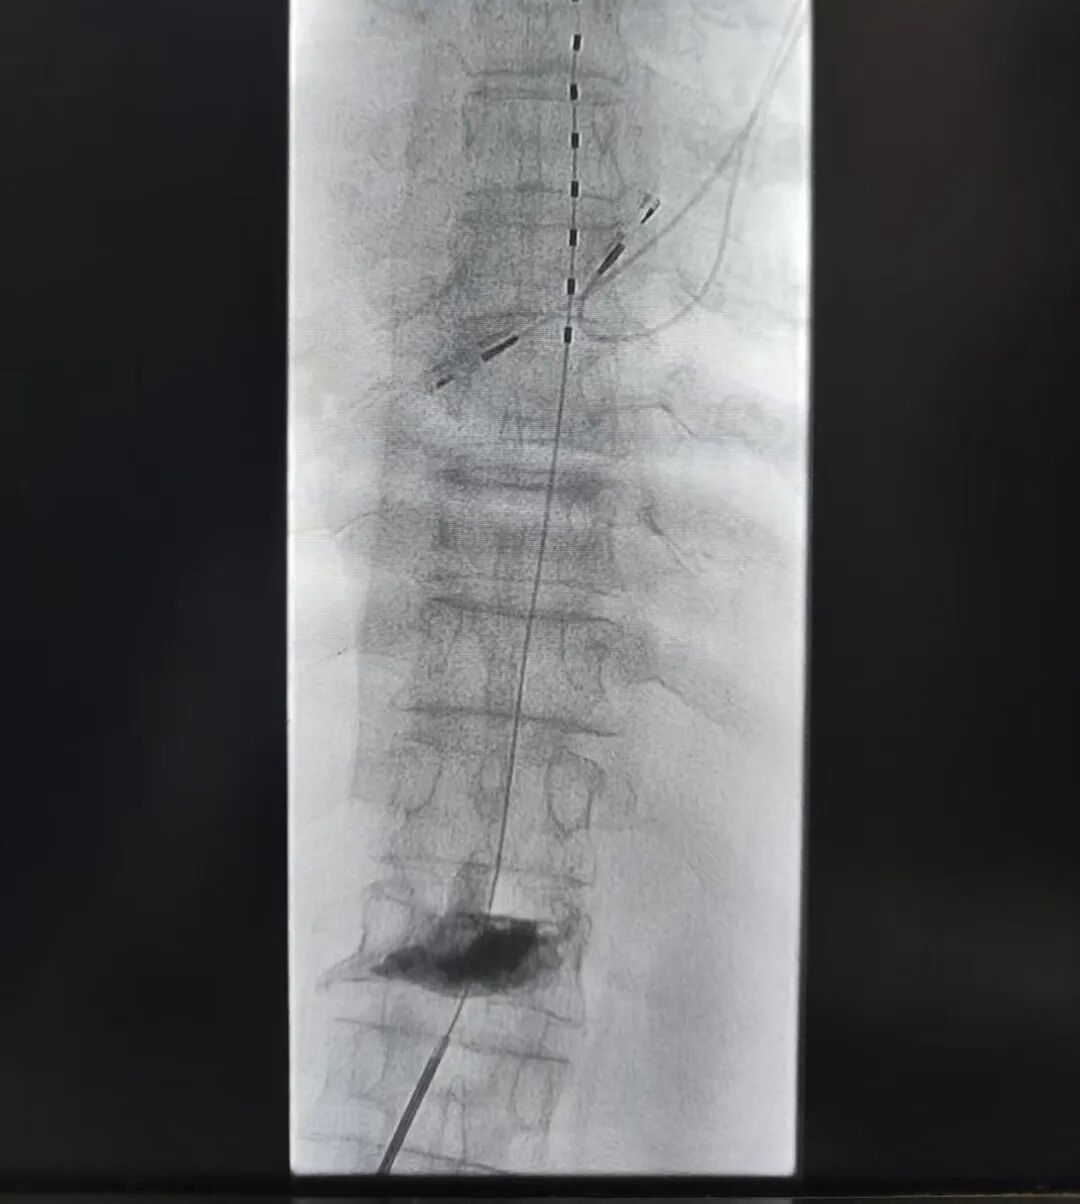

脊髓电刺激(SCS) 作为终极武器,好比在疼痛信号传导的“高速公路”上安装“智能交通管制系统”,通过电极发出的微电流阻断异常信号,用酥麻感替代剧痛。